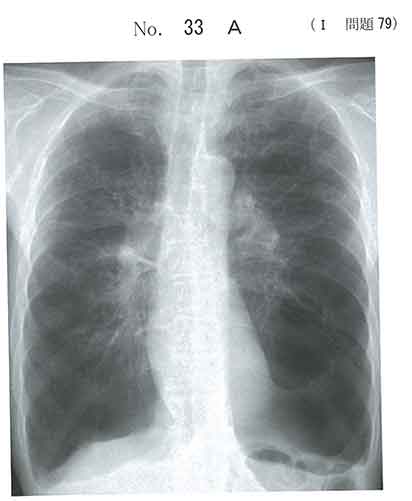

胸部x線で縦隔変位、左下肺野の血管陰影の欠損でCOPDから左気胸と考えましたが、

気胸は起きてないです?

左下は巨大ブラ?

左肺にあるのはジャイアントブラかと思われるので、ドレナージというか、穿刺は禁忌に近いです。

気胸はあるのでは?だからad